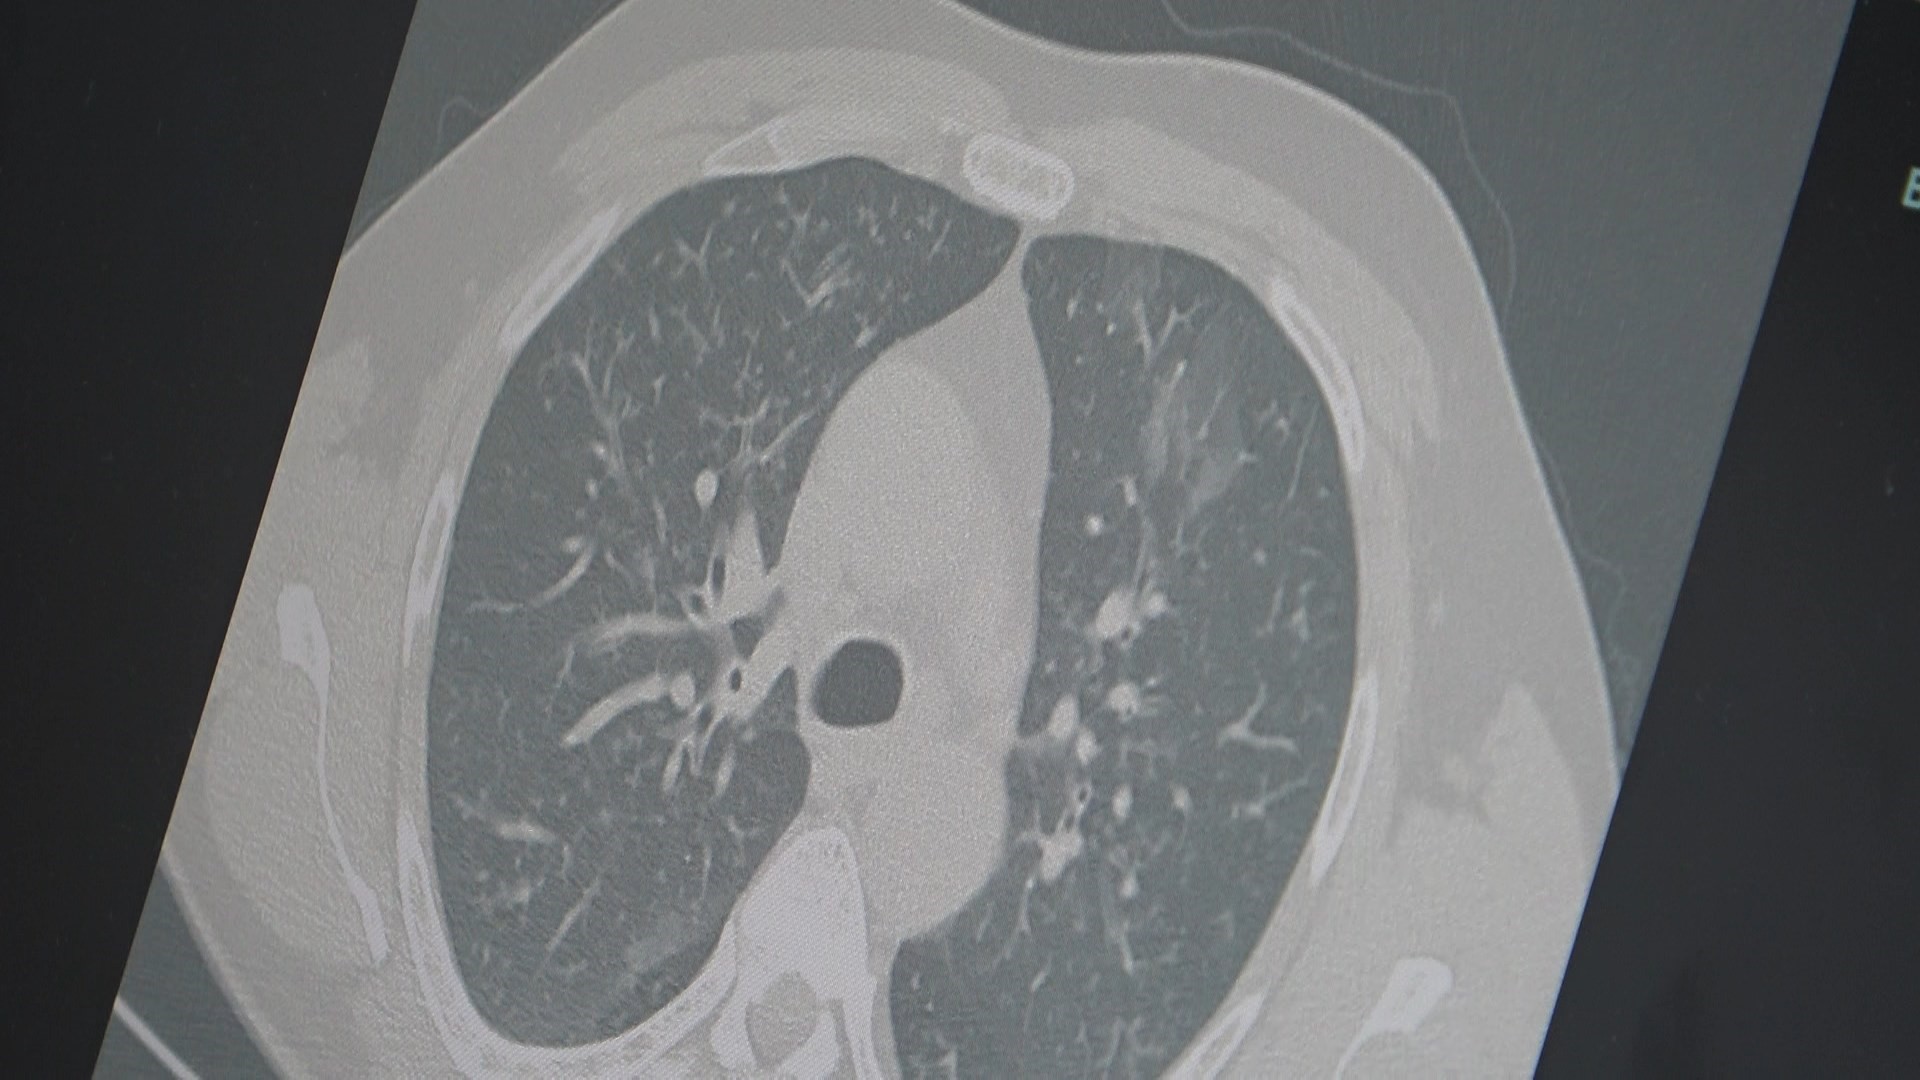

Prof. Dr. Özkaya, grip ve Kovid-19’un zatürreye dönüşme riskine işaret ederek, “Grip veya kovid sonrası birçok hastamızda hastalık akciğerlere iniyor ve zatürre olarak karşımıza çıkıyor. Hastaneye yatan hasta sayısında da artış gözlemliyoruz” dedi.

Özkaya, vatandaşlara şu önerilerde bulundu: “En ufak grip benzeri şikayeti olan vatandaşlarımızın evlerinde dinlenmelerini öneriyoruz. Uzamış öksürük ve nefes darlığı yaşayanların ise mutlaka doktora başvurarak akciğer röntgeni çektirmeleri ve uygun tedaviyi almaları gerekiyor.”